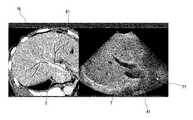

FIG. 11 shows, in form of a schematic diagram, one example of adisplay16 with anultrasound image71 with vessel information.FIG. 12 shows, in form of a picture, another example of adisplay16 with anultrasound image71 with vessel information. In each of the examples ofFIG. 11 andFIG. 12, theultrasound image71 or current B-mode image41 is a 2D B-mode image illustrating the target T in the anatomical region of interest. In this case, theportion61 is a 2D-slice of the 3D-vessel map, as can be seen inFIG. 11 orFIG. 12. The invasive medical device (not shown inFIG. 11 orFIG. 12) may also be visible in the image during an image guidance procedure.

In the example ofFIG. 11, theultrasound image71 is provided by overlaying the current B-mode image41 and the selectedportion61 of the 3D-vessel map. In this case, theimage processing unit70 is configured to overlay or fuse the current B-mode image41 and the selectedportion61 of the 3D-vessel map51 to provide theultrasound image71 with overlaid vessel information, which can then be displayed. Thus, theultrasound image71 has overlaid vessel information. In other words, the vessel information or portion of the 3D-vessel map61 is directly overlaid onto or incorporated into the ultrasound image. Theultrasound image71 comprises vessel information, overlaid on the 2D B-mode image41, in the form of theportion61 of the 3D-vessel map. In this example ofFIG. 11, the vessel information orportion61 is illustrated in form of the outlines of the vessel. However, it will be understood that the vessel information can be presented in any other suitable manner, such as for example a line running along the center of the vessel or colorizing the vessel within the boundaries of the outline.

In the example ofFIG. 12, theultrasound image71 is provided by having the current (or live) B-mode image41 and the selectedportion61 of the 3D-vessel map in a side by side format or representation. InFIG. 12, the current (or live) B-mode image41 is presented as a first image portion on the right side of thedisplay16 and the selectedportion61 is presented in a second image portion on the left side of thedisplay16. In this case, theimage processing unit70 is configured to add the current B-mode image41 and the selectedportion61 of the 3D-vessel map51 next to each other to provide theultrasound image71 with vessel information, which can then be displayed. The selectedportion61 or vessel information can for example be in a previously acquired registered image (e.g. color image). In one example, the selectedportion61 can be presented or contained in CT data or MR data (seeFIG. 12), as will be explained in further detail with reference toFIG. 8. In another example, the selectedportion61 can be presented or contained in an ultrasound image, as will be explained in further detail with reference toFIG. 6 orFIG. 7. In this example of FIG.12, the vessel information orportion61 is illustrated in form of a line running along the center of the vessel. However, as mentioned above, it will be understood that the vessel information can be presented in any other suitable manner.